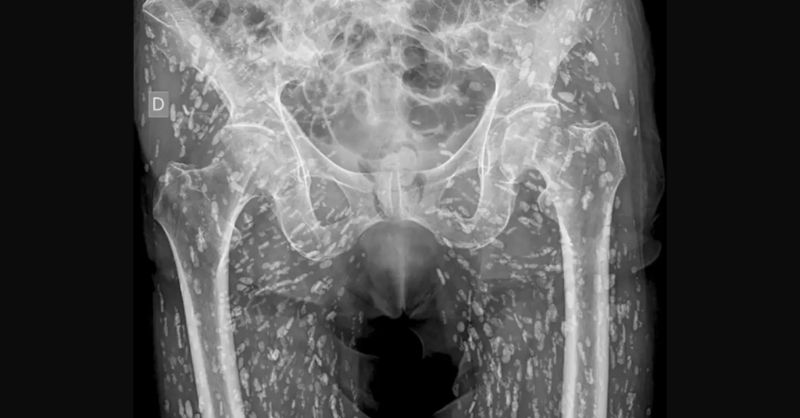

Wash Your Hands or You Could End Up Full of Tapeworms Like This Guy

A patient walked into the ER complaining of hip pain after a nasty fall. They walked out with a shocking diagnosis: their body was filled with calcified parasites....